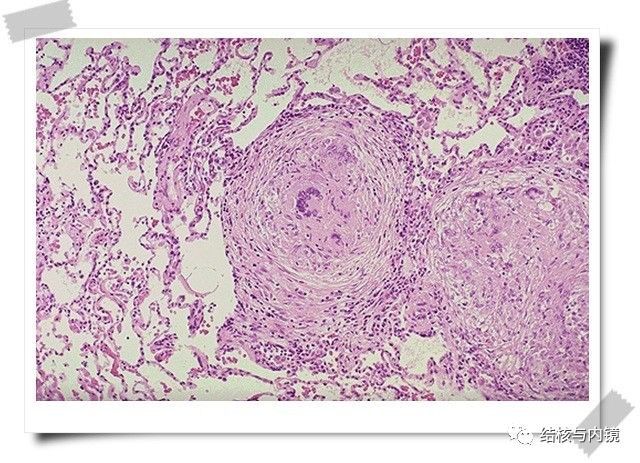

常规支气管镜获取标本进行相关检测可实现肺结核的早期诊断。

支气管镜下多种联合检测可提高菌阴肺结核早期诊断率,避免漏诊及误诊。BALF行Xpert MTB/RIF检测在涂阴肺结核中的敏感度/特异度均较高,且检测快速并能判断是否利福平耐药。

目前大多数学者建议:对所有肺结核及可疑肺结核患者均应常规进行支气管镜检查,全部病例均在可疑部位活检/刷检并镜下吸痰或灌洗留取标本,进行组织学/细胞学和病原学检测。